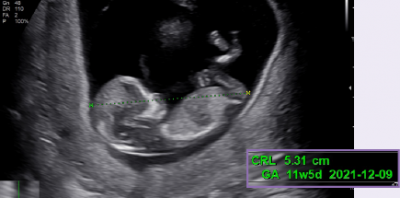

Měření NT pomocí automatické detekce střední sagitální roviny

Při měření nuchální translucence (NT) plodu v prvních týdnech těhotenství, poskytuje 5D NT™ automatické zobrazení ve středoagitální rovině otáčením a zvětšováním snímků.